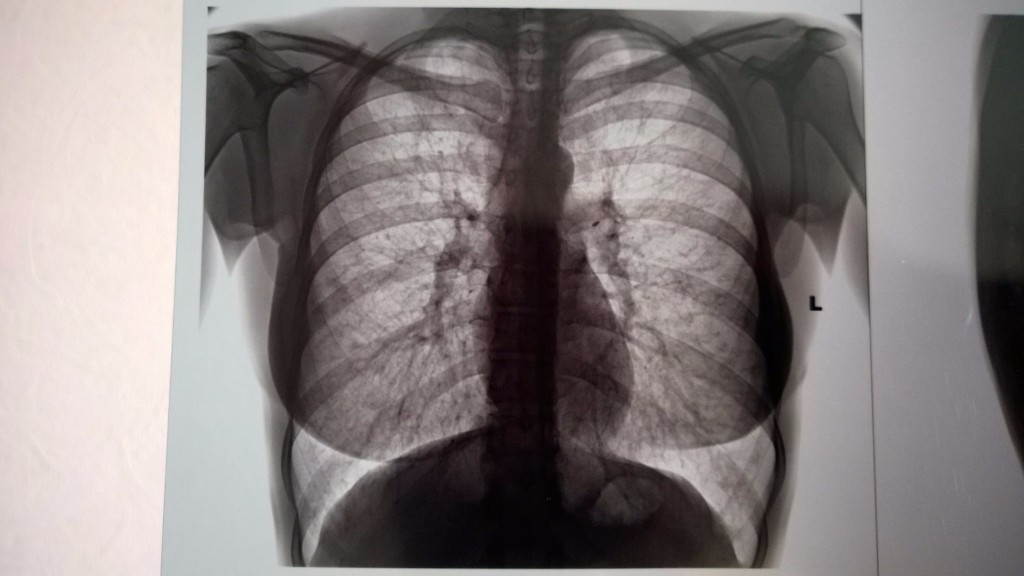

Рентген здоровых легких: примеры снимков и советы

Раздел: Сокровищница опыта